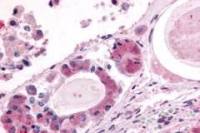

p38 antibody [N1C3-2] detects p38 protein at nucleus on human lung adenocarcinoma by immunohistochemical analysis.

Sample: Paraffin-embedded human lung adenocarcinoma.

p38 antibody [N1C3-2] (GTX110720) diluted at 1:250.

Antigen Retrieval: Citrate buffer, pH 6.0, 15 min